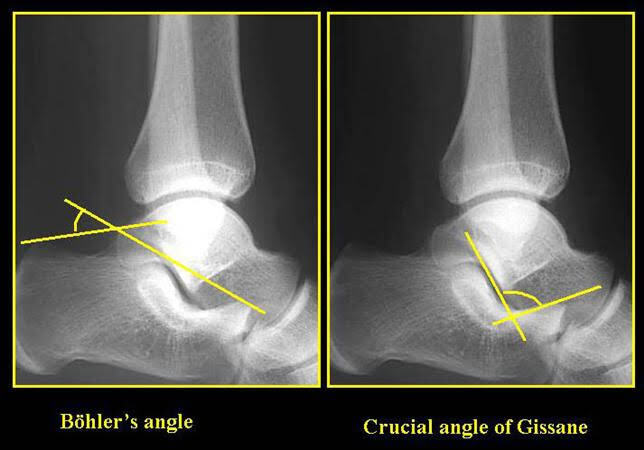

Normal value for Bohler angle and critical angle of Gissane (degrees) for calcaneal fracture assessment

20-40 and 120-140